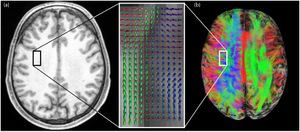

Publication: PLoS One. 2015 Oct 7;10(10):e0139434. PMID: 26444010 | PDF Authors: Tax CM, Chamberland M, van Stralen M, Viergever MA, Whittingstall K, Fortin D, Descoteaux M, Leemans A. Institution: Image Sciences Institute, University Medical Center Utrecht, Utrecht, The Netherlands. Background/Purpose: Fiber tractography plays an important role in exploring the architectural organization of fiber trajectories, both in fundamental neuroscience and in clinical applications. With the advent of diffusion MRI (dMRI) approaches that can also model "crossing fibers", the complexity of the fiber network as reconstructed with tractography has increased tremendously. Many pathways interdigitate and overlap, which hampers an unequivocal 3D visualization of the network and impedes an efficient study of its organization. We propose a novel fiber tractography visualization approach that interactively and selectively adapts the transparency rendering of fiber trajectories as a function of their orientation to enhance the visibility of the spatial context. More specifically, pathways that are oriented (locally or globally) along a user-specified opacity axis can be made more transparent or opaque. This substantially improves the 3D visualization of the fiber network and the exploration of tissue configurations that would otherwise be largely covered by other pathways. We present examples of fiber bundle extraction and neurosurgical planning cases where the added benefit of our new visualization scheme is demonstrated over conventional fiber visualization approaches. Funding:

Cluttered fiber tractography visualizations due to the ability to resolve “crossing fibers” at a voxel level and the great overlap of pathways. (a) At the location of the square in the anatomical T1-weighted image (left), the dODFs (visualized as spherical “glyph” representations overlaid on a fractional anisotropy map in the magnified box on the right) reveal fiber crossings at the voxel level [42]. (b) Left hemisphere: pathways greatly overlap, resulting in a cluttered view (superior) in which underlying pathway configurations are hidden. The square indicates the same location as in (a). Right hemisphere: orientation-dependent transparency rendering in which all streamline segments that run in the direction of the viewing axis are rendered transparent. In this way, the underlying structures are revealed and can be explored. |